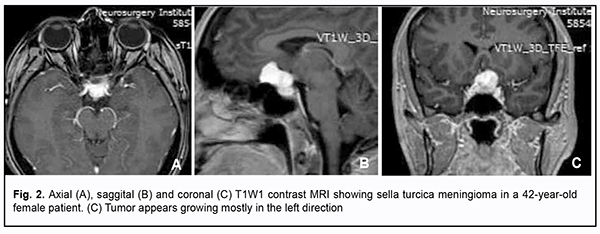

Introduction Skull-base tumors (SBTs) of the middle and anterior fossae typically cause mass effect on the optic nerve/chiasm complex. The most common of these neoplasms are pituitary adenomas, meningiomas and craniopharyngiomas [1, 2, 3, 4]. Chiasmal compression is accompanied by a gradual decrease in visual acuity, bitemporal visual field defects and development of primary descending optic atrophy (OA) [5, 6]. Clinical manifestations of SBTs vary and depend on tumor involvement, nature of growth pattern, and rate of growth. Impaired visual functions are observed in 67.8-83% of patients. Specifically, reduced visual acuity and visual field impairment have been found in 38-68.5% and 68-70%, respectively, of patients [5, 7, 8, 9]. 30-88.9% of cases manifest loss of visual acuity or visual fields [5, 9, 10]. Late-diagnosed but mostly benign processes causing compression of the optic nerve/chiasm complex may result in temporary or permanent visual function loss leading to visual disability. Prolonged chiasmal compression results in the development of OA in 26.7% to 72% of patients, leading to blindness in 3.5% to 25% of cases [4, 10, 11, 12]. Significant or rapidly progressive loss of visual acuity and/or visual fields in the presence of a small tumor may suggest malignancy. Despite progress in neuroimaging techniques, the number of new annually registered cases of primary optic atrophy (OA) associated with SBT and partial or complete loss of visual acuity and/or visual fields, is steadily increasing, making the issue increasingly important [5, 10, 12]. The purpose of the study was to investigate neuroophthalmological symptoms in patients with skull-base tumors. Material and Methods This retrospective study included the records of 500 patients (1000 eyes; 270 (54%) women and 230 (46%) men; aged 14 to 74 years; mean age, 51 ± 0.8 years) who received treatment for SBT and loss of visual acuity and/or visual fields at the Transsphenoidal Neurosurgery Department, Romodanov Neurosurgery Institute, during the period from 2017 through 2019. The inclusion criterion was surgical evidence of SBT. Patients underwent clinical and neurological, eye, and otoneurological examination (a routine otoneurological examination with assessment of cranial nerve function). Instrumental and laboratory studies were conducted. Neuroimaging included sella turcica X-ray study with AXIOM Iconos R100 (Siemens) or Radrex-I (Toshiba) in 72 patients, brain magnetic resonance imaging (MRI) with a 1.5-T MRI system (Intera 1.5T/I system, Philips Medical Systems, Best, the Netherlands) in all patients, and computed tomography (CT). The MRI of brain and pituitary gland were obtained using T1-weighted image (WI) and T2WI. Neuro-ophthalmic examination included best-corrected visual acuity assessment, biomicroscopy, static automated and kinetic perimetry, and direct and indirect ophthalmoscopy. Best-corrected visual acuity was classified as normal (1.0), mild impairment (0.7-0.9), moderate impairment (0.4-0.6), severe impairment (0.1-0.3), and very severe impairment (< 0.1). Static automated perimetry (SAP) was performed with the Centerfield 2 Perimeter (Oculus, Wetzlar, Germany) using the neurological 30-2 threshold test program and Neuro screening program. Aside from defect localization, the arithmetic mean of the sensitivity loss, the mean defect (MD), was used to assess visual field loss severity. Visual field loss severity was classified as “no visual field loss” (Grade 0; normal visual field), mild visual field loss (Grade 1; MD, –2 dB to –4 dB), moderate visual field loss (Grade 2; MD, –4 dB to –12 dB), severe visual field loss (Grade 3; MD, –12 dB to –20 dB), and very severe visual field loss (Grade 4; MD, worse than –20 dB). The visual field loss was classified as very severe if it was not possible to assess visual fields due to the extremely poor visual function. A chiasmal syndrome was considered symmetric if both eyes had the same grade of visual field loss. In addition, a chiasmal syndrome was considered asymmetric if the difference between eyes in grade of visual field loss severity was 1, and it was considered markedly asymmetric if the difference was 2 or greater. Eye movements in each of the four directions of gaze were assessed. Visual acuity was assessed with a diaphragm if there was mydriasis caused by oculomotor nerve palsy. This study followed the ethical standards stated in the Declaration of Helsinki and was approved by the Local Ethics Committee of the Romodanov Institute. Written informed consent was obtained from all individuals enrolled in the study. Results are presented as the mean and standard deviation (M ± SD). Student’s unpaired t test was used to determine differences between independent groups. The level of significance p ≤ 0.05 was assumed. Results and Discussion Loss of visual acuity and/or visual fields was found in 500 (100%) patients. Pituitary adenoma (PA) was the most common tumor-causing loss of visual acuity or visual fields (420 patients; 84%; Fig. 1), followed by sella turcica meningioma (35 patients; 7%; Fig. 2), craniopharyngioma (33 patients; 6%; Fig. 3), chiasmal glioma (8 patients; 2%), germinoma and teratoma (4 patients; 1%). There was surgical evidence both of suprasellar extension of the SBT and of compression of the optic nerve/chiasm complex in all patients.

All the 420 patients with PA exhibited loss of visual acuity in one or two eyes: in 96 (22.9%%) patients, only one eye had a VA lower than 1.0; in 268 (63.8%), both eyes had a VA lower than 1.0; in 32 (7.6%), one eye had a VA lower than 1.0, and another, a VA lower than 0.1; in 24 (5.7%), both eyes had a VA lower than 0.1. Best-corrected visual acuity was normal (1.0) in 96 (11.4%) eyes, mildly impaired (0.7-0.9) in 224 (26.6%) eyes, moderately impaired (0.4-0.6) in 226 (26.9%) eyes, severely impaired (0.1-0.3) in 214 (25.5%) eyes, and very severely impaired (< 0.1) in 80 (9.6%) eyes. In addition, 70 eyes (8.3%) were blind and 5 patients were bilaterally blind. Static perimetry found no changes in 43 (5.2%) eyes. Temporal hemianopia (either complete or partial) only was the commonest field defect (385 eyes; 45.9%), followed by temporal hemianopia with central scotoma (205 eyes; 24.6%), central scotoma only (58 eyes; 6.9%), and residual visual field in the nasal inner quadrant, with a loss of central vision (79 eyes; 9.5%). Visual field was not measurable due to extremely low visual function in 70 (8.3%) eyes. Loss of sensitivity to light was classified as mild in 132 (15.7%) eyes, moderate in 416 (49.5%) eyes, and severe and very severe in 174 (20.7%) eyes and 75 (8.9%) eyes, respectively. No loss of sensitivity to light was seen in 43 (5.1%) eyes. Ophthalmoscopy found primary descending OA in 212 (50.5%) patients. Of these, 188 patients (376 eyes) exhibited bilateral OA, and 24 patients (24 eyes), unilateral OA. Symmetric, asymmetric and markedly asymmetric chiasmal syndrome was found in 268 (63.8%), 114 (27.1%), and 38 (9.1%) patients, respectively. Ocular motility disorders (OMD) were found in 34 (8.1%) patients. Of these patients, 6 (17.6%) had isolated unilateral CNIII (oculomotor nerve) palsy, 19 (55.9%) had isolated unilateral CNVI (abducens nerve) palsy, and 9 (26.5%) had combined oculomotor and abducens nerve palsy. Sella turcica meningioma was found in 35 (100%) patients. Of these, 8 (22.9%) had the tumor with optic canal involvement. In addition, the commonest complaint was gradually decreased vision for 3 months to 2 years. Visual acuity loss was mostly asymmetric: in 15 (42.9%) patients, one eye had a VA of 1.0, and another, a VA lower than 1.0; in 9 (25.7%), both eyes had a VA lower than 1.0; in 8 (22.9%), one eye had a VA of 1.0, and another, a VA lower than 0.1; and in 3 (8.6%), one eye had a VA lower than 1.0, and another, a VA lower than 0.1. Best-corrected visual acuity was normal (1.0) in 23 (32.9%) eyes, mildly impaired (0.7-0.9) in 11 (15.7%) eyes, moderately impaired (0.4-0.6) in 9 (12.8%) eyes, severely impaired (0.1-0.3) in 17 (24.3%) eyes, and very severely impaired (< 0.1) in 10 (14.3%) eyes. Temporal hemianopia (either complete or partial) only was the commonest field defect (23 eyes; 32.9%), followed by temporal hemianopia with central scotoma (13 eyes; 18.6%), residual visual field in the inner half (10 eyes; 14.3%), residual visual field in the outer half (5 eyes; 7.1%), nasal hemianopia (4 eyes; 5.7%), lower hemianopia (2 eyes; 2.9%), and central scotoma only (1 eye; 1.4%). In addition, no visual field defect was found in 11 (15.7%) eyes. Visual field was not measurable due to extremely low visual function in 1 (1.4%) eye. Loss of sensitivity to light was classified as mild in 22 (31.4%) eyes, moderate in 9 (12.9%) eyes, and severe and very severe in 13 (18.6%) eyes and 15 (21.4%) eyes, respectively. No loss of sensitivity to light was seen in 11 (15.7%) eyes. Ophthalmoscopy found OA in 31 (88.6%) patients. Of these, 28 patients (28 eyes) exhibited unilateral OA, and 3 patients (6 eyes), bilateral OA. Symmetric, asymmetric and markedly asymmetric chiasmal syndrome was found in 3 (8.6%), 9 (25.7%), and 23 (65.7%) patients, respectively. Ocular motility disorders were found in two patients. These two had isolated unilateral partial CNIII palsy. Among the 33 patients with supradiaphragmatic craniopharyngioma, symmetric chiasmal syndrome was the most common (19 patients; 57.6%), followed by asymmetric (8 patients; 24.2%) and markedly asymmetric (6 patients; 18.2%) chiasmal syndrome. In 12 (36.4%) patients, only one eye had a VA lower than 1.0; in 11 (33.3%), both eyes had a VA lower than 1.0; in 3 (9.1%), one eye had a VA of 1.0, and another, a VA lower than 0.1; in 4 (12.1%), one eye had a VA lower than 1.0, and another, a VA lower than 0.1; and in 3 (9.1%), both eyes had a VA lower than 0.1. Best-corrected visual acuity was normal (1.0) in 15 (22.7%) eyes, mildly impaired (0.7-0.9) in 8 (12.1%) eyes, moderately impaired (0.4-0.6) in 13 (19.7%) eyes, severely impaired (0.1-0.3) in 18 (27.3%) eyes, and very severely impaired (< 0.1) in 12 (18.2%) eyes. Visual field defects were found in all eyes with supradiaphragmatic craniopharyngioma: central temporal scotoma was the commonest field defect (23 eyes; 32.9%), followed by temporal hemianopia (either complete or partial) only (12 eyes; 18.2%), temporal hemianopia with central scotoma (11 eyes; 16.6%), homonymous hemianopia (10 eyes; 15.2%), residual visual field in the inner half (5 eyes; 7.6%), and central scotoma only (2 eyes; 3%). In addition, visual field was not measurable in 4 (6.1%) eyes. Loss of sensitivity to light was classified as mild in 15 (22.7%) eyes, moderate in 17 (25.8%) eyes, and severe and very severe in 16 (24.2%) eyes and 18 (27.3%) eyes, respectively. Ophthalmoscopy found OA in 25 (75.8%) patients. Of these, 20 patients (40 eyes) exhibited bilateral OA, and 5 patients (5 eyes), unilateral OA. OMD were found in 3 patients. Of these patients, one had isolated unilateral partial CNIII palsy and two had isolated unilateral partial CNVI palsy. Therefore, the major sign of SBT is a gradual development of chiasmal syndrome, which is accompanied by decreased visual acuity, bitemporal visual field defects and development of primary compressive OA. Our findings for a large sample of SBTs of the middle and anterior fossae are in general agreement with those from the literature; however, most of these studies reported on significantly smaller samples [3, 4, 6, 7, 8, 10]. We found significant differences among pituitary adenoma, sella turcica meningioma and supradiaphragmatic craniopharyngioma groups (groups of the three most common skull-base tumors of the middle and anterior fossae) with regard to the features of the chiasmal syndrome and compression of the optic nerve/chiasm complex. Pituitary adenoma was most commonly associated with a symmetric chiasmal syndrome (63.8%), which developed either gradually or gradually or (in a stroke-like course of tumor progression) abruptly. In addition, it was accompanied by a symmetric loss of visual acuity (77.1%), visual field defects (89.8%) and development of OA (50.5%). In patients with sella turcica meningioma, chiasmal syndrome most commonly was markedly asymmetric (65.7%), developed for a long time (several years) and gradually, and accompanied by mild loss of both visual acuity and visual fields in one eye, and severe or very severe visual acuity loss, residual visual field and OA in the fellow eye. The principal pathogenetic mechanism for optic neuropathy relates to compression of the optic nerve/chiasm complex (mostly, of the anterior chiasm). Patients with supradiaphragmatic craniopharyngiomas had various amounts of loss of visual acuity and/or visual fields, and, most commonly, symmetric chiasmal syndrome and bilateral optic atrophy. In addition, the posterior chiasm (especially, the papillomacular bundle) was affected, which was manifested by bitemporal central scotoma (33.3%) and homonymous hemianopia (15.2%). The pathogenesis of impaired visual functions in patients with these tumors relates to chiasmal compression by a cystic tumor component, devascularization of the optic chiasm, and chiasmal tumor growth. Thus, there are ophthalmological features of disease course in various histologic types of skull-base tumors. Loss of visual acuity and/or visual fields was an early and major symptom in the clinical picture of disease. The role of the ophthalmologist in the early diagnosis of and monitoring of patients with skull-base tumors should be noted.